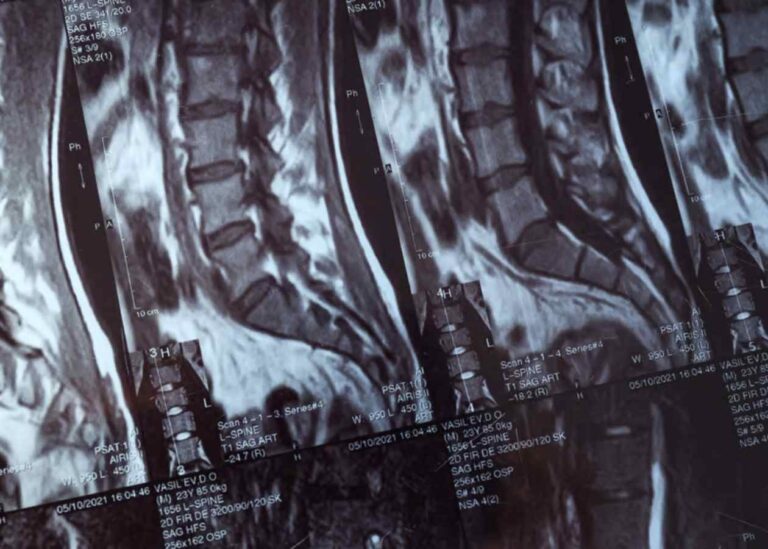

Omurga sistemi, vücudumuzun hem temel taşıyıcı kolonu hem de sinir iletim hattını koruyan hayati bir yapıdır.…

Bel sağlığı, yaşam kalitemizi doğrudan etkileyen en temel unsurların başında gelir. Ancak bazen omurgamızdaki dizilim bozulur…

Yaşam kalitesini ciddi oranda etkileyen, hareket kabiliyetini kısıtlayan ve genellikle yaşlanmaya bağlı olarak gelişen spinal kanal…